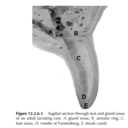

Mammary gland and Teat Anatomy .png

Teat section .png